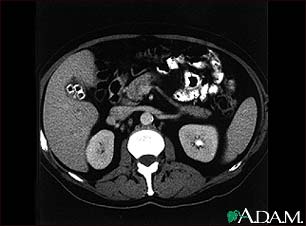

Cholecystolithiasis. CT scan of the upper abdomen showing multiple gallstones.